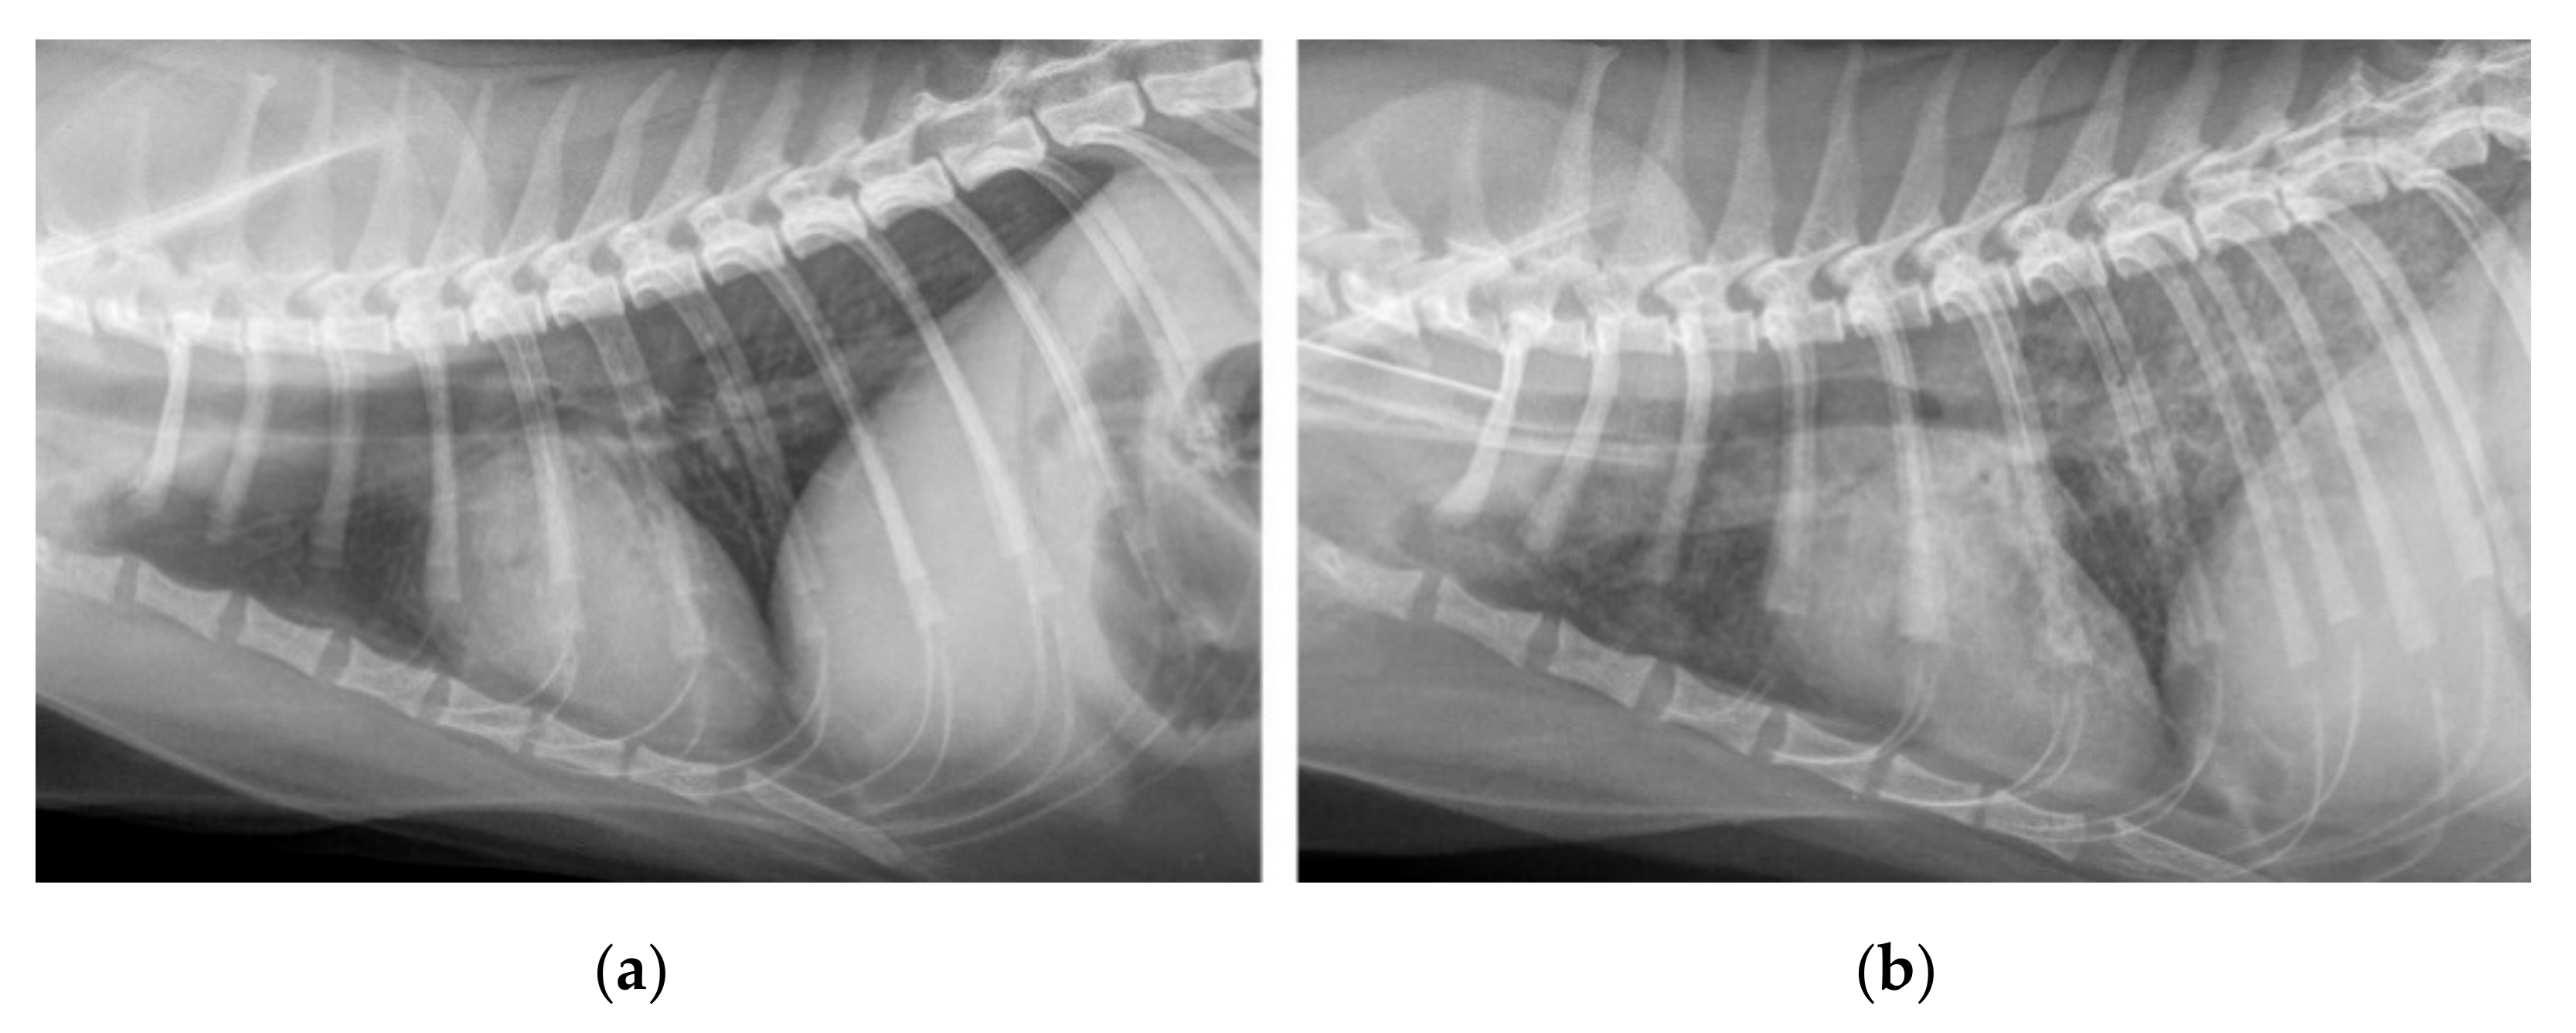

2.5. Radiography